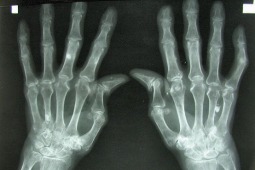

Amerykańscy pacjenci z RZA odstawiają leki biologiczne

Połowa z amerykańskich pacjentów, którzy podjęli leczenie reumatoidalnego zapalenia stawów (RZA) lekami biologicznymi – odstawiło je w ciągu dwóch lat stosowania – wynika z amerykańskich danych rejestrowych. Najczęściej podawanym przez pacjentów powodem odstawienia leku był „brak skuteczności”.